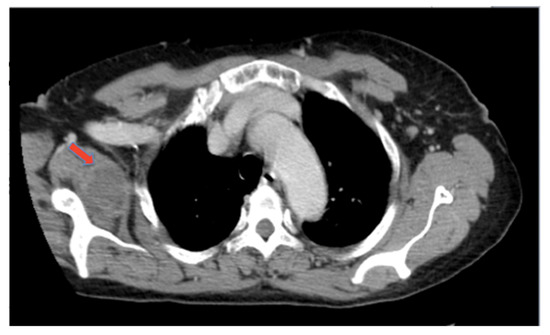

:1. Introduction